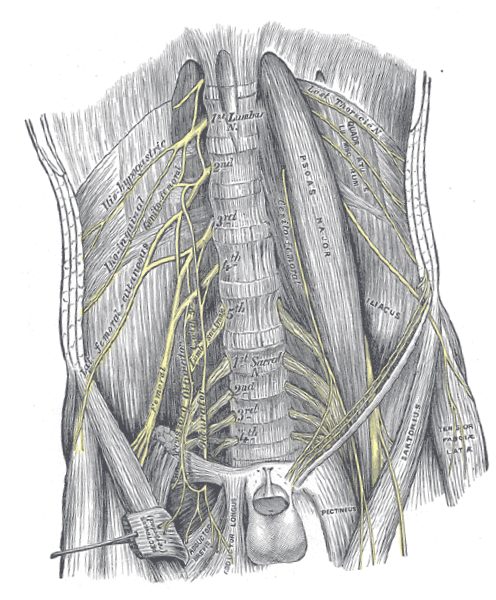

General anatomy of the lumbar plexus (Figure 2): The lumbar plexus primarily comprises the ventral rami of spinal nerves L1 to L4, with occasional contributions from the T12 nerve root (via the subcostal nerve) [6]. It is located within the posterior compartment of the psoas major muscle, anterior to the transverse processes of the lumbar vertebrae [7]. The nerve branches typically emerge through or around the psoas major, making this region particularly important in planning the trajectory for lead implantation during Xtra4.

General anatomy of the sacral plexus (Figure 2): The lumbosacral plexus is formed by the lumbar plexus (L1–L4) and the sacral plexus (L4–S4), interconnected via the lumbosacral trunk (L4–L5) [11]. The sacral portion of the plexus lies on the anterior surface of the piriformis muscle, deep within the pelvis, and contributes to the innervation of the lower extremities, pelvis, and perineum [8].

Figure 2. Anatomical illustration of the human lumbosacral plexus and iliopsoas complex. The figure highlights the spatial relationships between the nerves and surrounding anatomical structures, which are critical for accurate placement of extraforaminal spinal nerve stimulation leads in the lumbar region. Source: Gray, H. (1918). Gray's Anatomy: Descriptive and Surgical, 20th edition, Plate 823. Available at: https://upload.wikimedia.org/wikipedia/commons/7/7c/Gray823.png